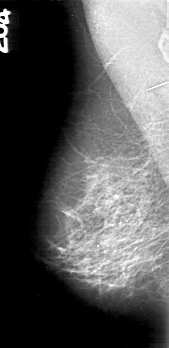

D_4162_1.RIGHT_MLO

LEFT_MLO LINES 5386 PIXELS_PER_LINE 2581 BITS_PER_PIXEL 12 RESOLUTION 43.5 OVERLAY

LESION_TYPE CALCIFICATION TYPE PLEOMORPHIC DISTRIBUTION CLUSTERED

ASSESSMENT 0

SUBTLETY 4

PATHOLOGY MALIGNANT